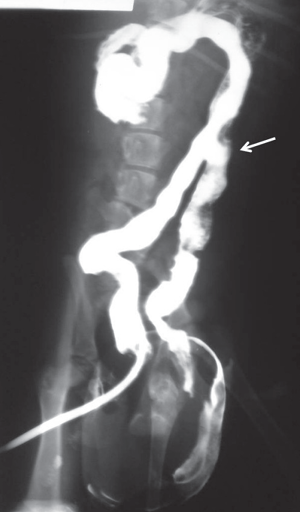

칼라 사진이었으면 더 분명해 보였겠지만 이 친구는 항문 주변으로 다리가 하나 더 있는 상태이다.

방사선 사진상으로는 다리뿐 아니라 장골이 하나 더 존재하는 상태로 관찰된다.

중복결장 또한 관찰되는 친구다.